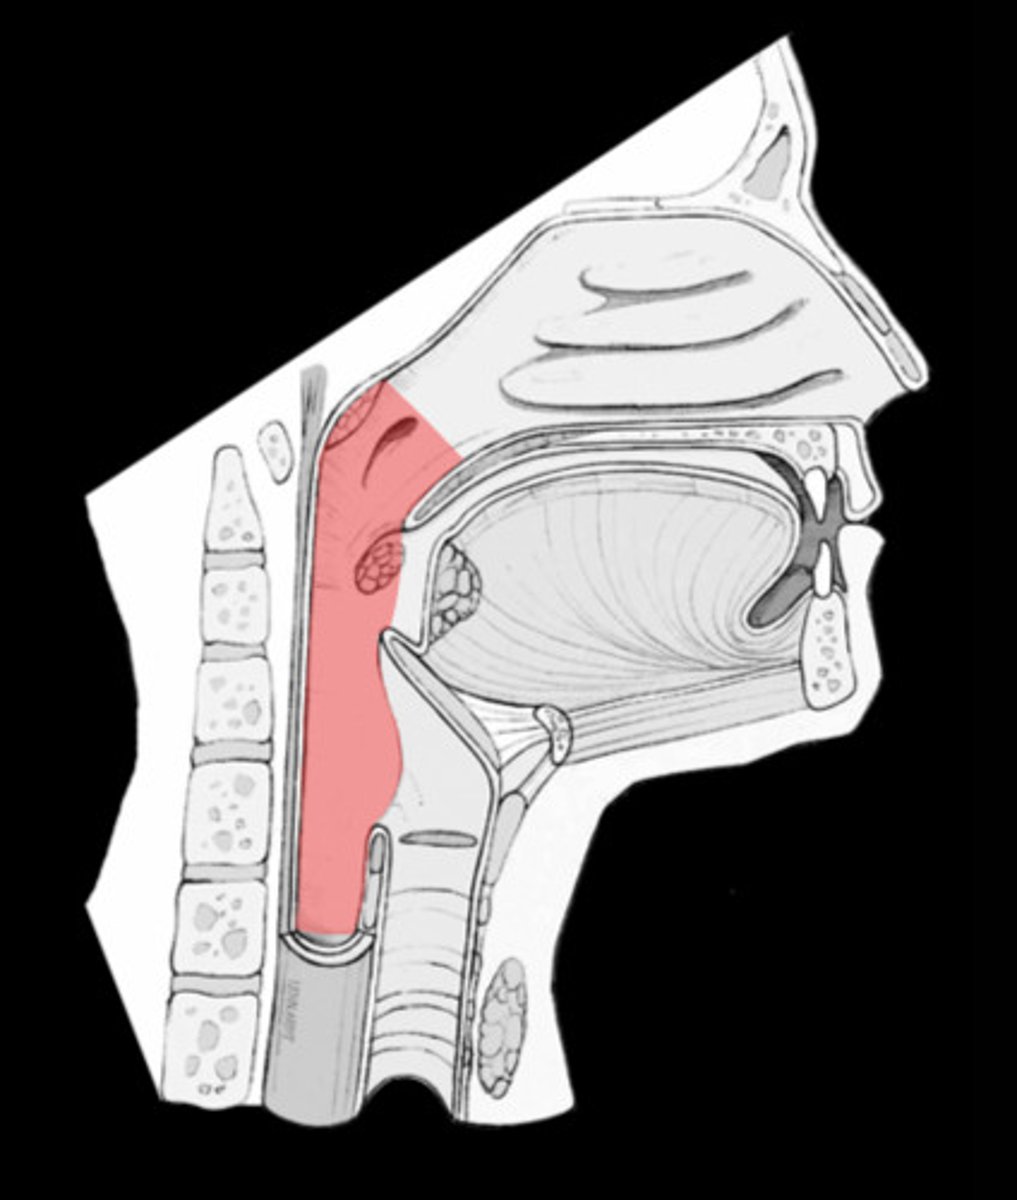

pharynx

serves as a food and air passageway. Air enters from the nasal cavities and/or mouth and passes through the pharynx to the larynx. Food enters the pharynx from the mouth and passes into the esophagus. (also called the throat)